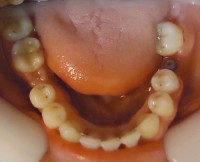

24- Vista final lateral dercho con colocacion de implante pieza 4.6 24- Vista final lateral dercho con colocacion de implante pieza 4.6 Deja un comentarioYou must be logged in to post a comment.